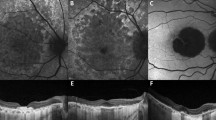

The aim of this study was to trace the evolution of geographic atrophy (GA) by clinical documentation and by clinico-morphological correlation in representative eyes. Geographic atrophy commonly commenced within a parafoveal band of incipient atrophy of varying width, characterised by semisolid drusen and a microreticular pigment pattern. Progession of atrophy mostly skirted fixation and visual acuity was a poor guide to the functional impact, an estimate of the percentage of fovea involved proving a more useful clinical parameter. The rate of progression slowed once GA had involved all the retina affected by incipient atrophy and the risk of choroidal neovascularization appeared to decline.

An earlier histological classification of the evolution of GA is revised according to the ultras- tructural findings. Membranous debris was not previously recognised and its contribution to the findings in incipient atrophy and to dot-like drusen is described.